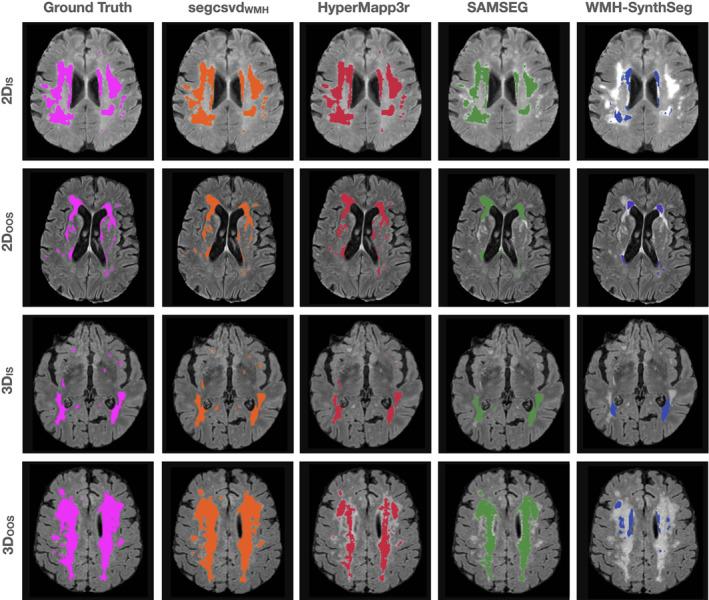

White matter hyperintensities (WMH) of presumed vascular origin are a magnetic resonance imaging (MRI)-based biomarker of cerebral small vessel disease (CSVD). WMH are associated with cognitive decline and increased risk of stroke and dementia, and are commonly observed in aging, vascular cognitive impairment, and neurodegenerative diseases. The reliable and rapid measurement of WMH in large-scale multisite clinical studies with heterogeneous patient populations remains challenging, where the diversity of imaging characteristics across studies adds additional complexity to this task. We present segcsvd, a convolutional neural network-based tool developed to provide reliable and accurate WMH quantification across diverse clinical datasets. segcsvd was developed using a large dataset consisting of over 700 fluid-attenuated inversion recovery MRI scans from seven multisite studies, spanning a wide range of clinical populations, WMH burdens, and imaging protocols. Model training incorporated anatomical information through a novel hierarchical segmentation approach, together with extensive data augmentation techniques to improve performance across varied imaging conditions. Benchmarked against three widely available segmentation tools, segcsvd demonstrated superior accuracy, achieving mean Dice score improvements of 7.8% ± 9.7% over HyperMapp3r, 21.8% ± 8.6% over SAMSEG, and 43.5% ± 7.1% over WMH-SynthSeg across four diverse test datasets. segcsvd also maintained consistently high Dice scores across these test datasets (mean DSC = 0.86 ± 0.08), and exhibited strong, stable correlations with periventricular, deep, and total WMH ground truth volumes (mean r = 0.99 ± 0.01). Additionally, segcsvd was robust to low and moderate levels of simulated MRI spike noise artifacts and maintained strong performance across a range of binary segmentation thresholds and WMH burden levels. These findings suggest that segcsvd may provide more accurate and robust WMH segmentation performance for heterogeneous clinical datasets characterized by varying degrees of CSVD severity.

推测为血管源性的脑白质高信号(WMH)是基于磁共振成像(MRI)的脑小血管疾病(CSVD)生物标志物。WMH与认知功能下降、中风和痴呆风险增加相关,且常见于衰老、血管性认知障碍和神经退行性疾病中。在具有异质性患者群体的大规模多中心临床研究中,可靠且快速地测量WMH仍然具有挑战性,因为各研究中成像特征的多样性给这项任务增加了额外的复杂性。我们展示了segcsvd,这是一种基于卷积神经网络开发的工具,旨在为不同的临床数据集提供可靠且准确的WMH定量分析。segcsvd是使用一个大型数据集开发的,该数据集包含来自7项多中心研究的700多次液体衰减反转恢复MRI扫描,涵盖了广泛的临床人群、WMH负荷和成像协议。模型训练通过一种新颖的分层分割方法纳入解剖学信息,并结合广泛的数据增强技术来提高在各种成像条件下的性能。与三种广泛使用的分割工具进行基准测试时,segcsvd表现出卓越的准确性,在四个不同的测试数据集上,其平均骰子系数得分比HyperMapp3r提高了7.8%±9.7%,比SAMSEG提高了21.8%±8.6%,比WMH-SynthSeg提高了43.5%±7.1%。segcsvd在这些测试数据集中也始终保持较高的骰子系数得分(平均DSC = 0.86±0.08),并且与脑室周围、深部和总的WMH真实体积表现出强而稳定的相关性(平均r = 0.99±0.01)。此外,segcsvd对低水平和中等水平的模拟MRI尖峰噪声伪影具有鲁棒性,并且在一系列二元分割阈值和WMH负荷水平上都保持了强大的性能。这些发现表明,对于以不同程度的CSVD严重程度为特征的异质性临床数据集,segcsvd可能提供更准确、更稳健的WMH分割性能。